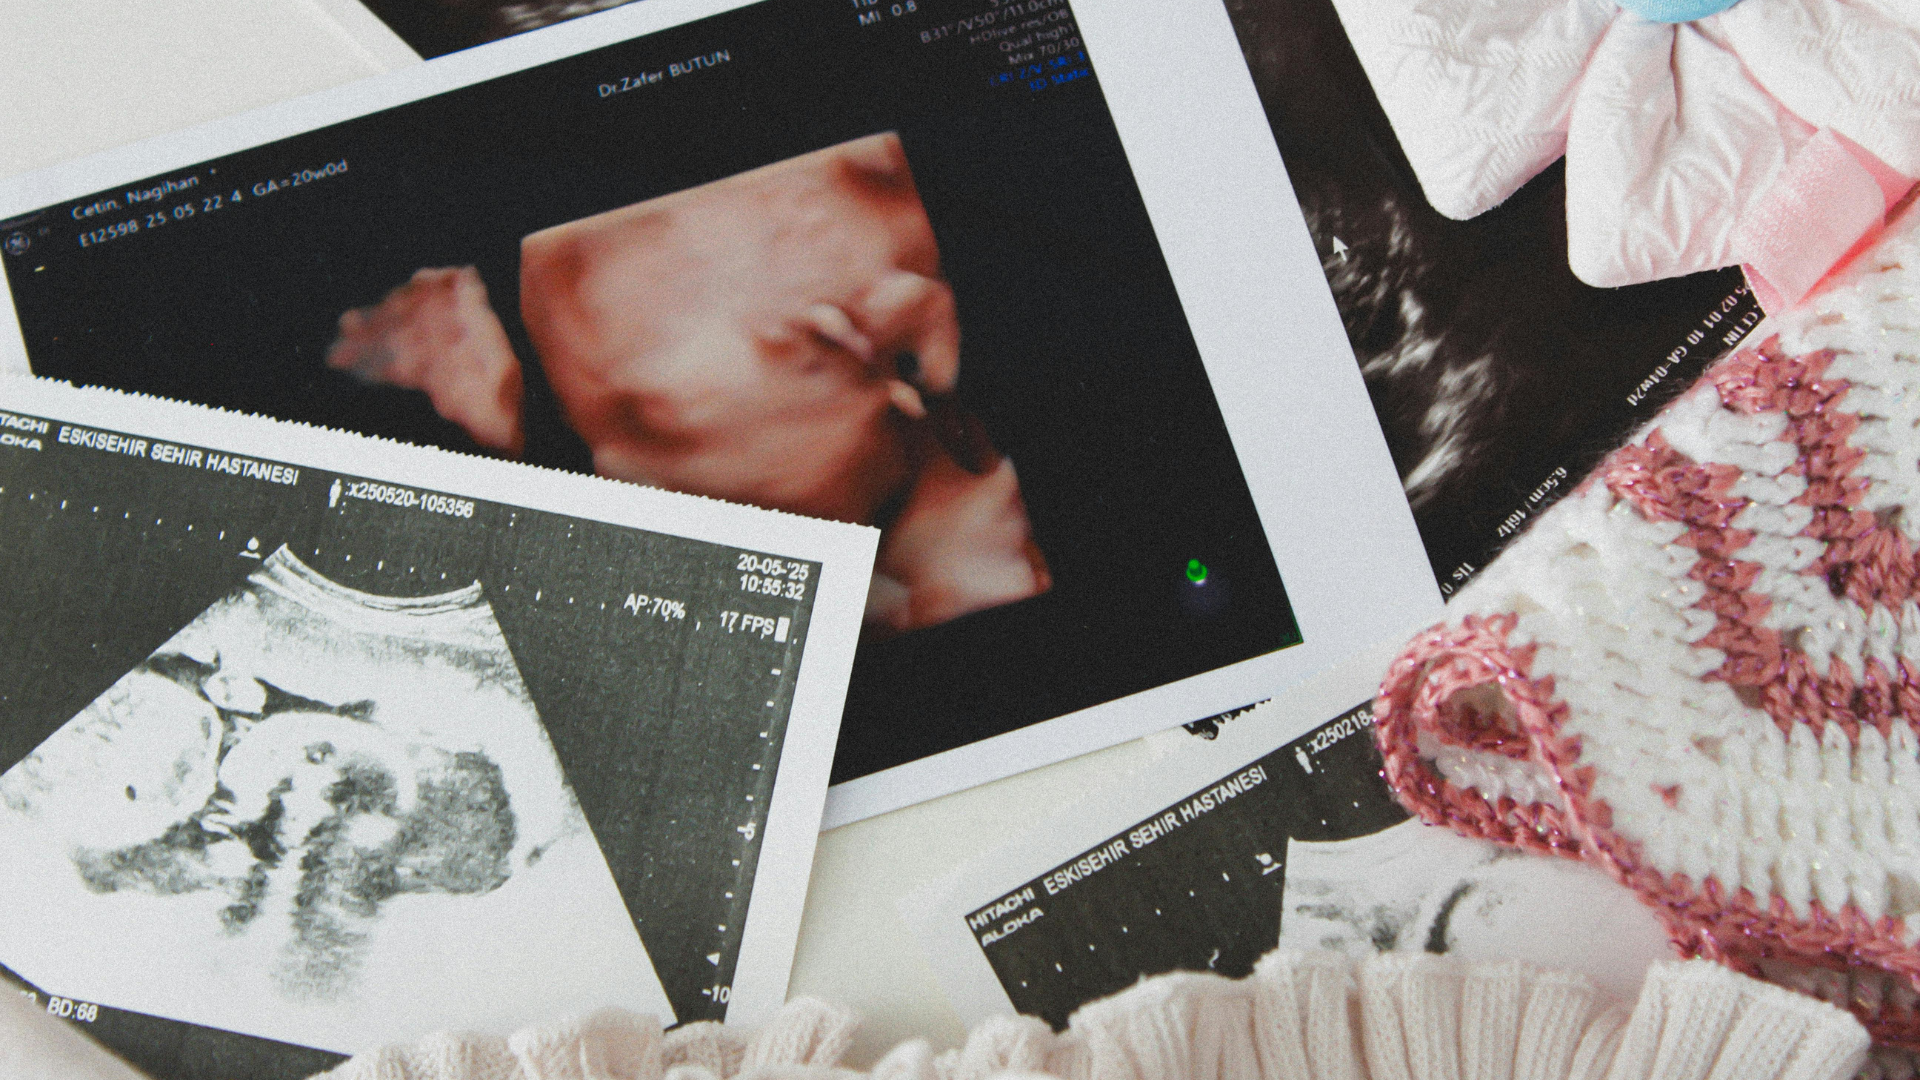

O ultrassom 4D é uma evolução tecnológica que acrescenta ao exame a dimensão do movimento em tempo real. Apesar de ser uma revolução durante o acompanhamento do bebê, o ultrassom 4D não é um substituto completo do ultrassom morfológico tradicional. Ambos têm suas vantagens e aplicações específicas.

As versões 3D e 4D do morfológico oferecem imagens tridimensionais e em movimento, permitindo melhor visualização da face e superfície corporal do bebê, mas não substituem a avaliação bidimensional tradicional para fins diagnósticos.

Na prática clínica, o 4D pode ser especialmente útil para confirmar e detalhar achados já identificados no morfológico — como suspeita de fenda palatina, por exemplo, em que a visualização tridimensional da face ajuda a dimensionar a extensão da alteração.

“O 4D oferece uma percepção mais nítida da anatomia superficial do bebê e cria uma conexão emocional muito forte entre os pais e o filho“, resume o Dr. Armênio Mekhitarian. “Mas o rastreamento de malformações internas, como cardíacas, cerebrais, renais, ainda depende da avaliação bidimensional criteriosa, com um profissional treinado e um equipamento adequado“.

A melhor época para fazer o ultrassom 3D ou 4D é entre a 26ª e a 29ª semana de gestação, pois nessas semanas o bebê já está crescido e ainda existe bastante líquido amniótico na barriga da mãe. Antes desse período, o feto ainda tem pouca gordura subcutânea, o que prejudica a definição das imagens.